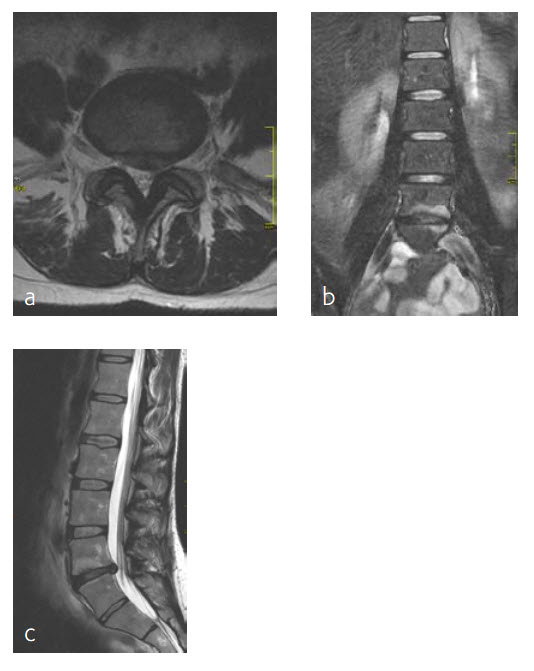

A 47-year-old woman was suffering chronic low back pain for several years, with severe pain attacks and with uncontrolled movements becoming increasingly disabling due to DD and erosive osteochondrosis at L4/L5. Condition after sciatica due to a disc herniation L4/L5, having nonoperative treatment. The MRI findings progressive compared to April 2014 are shown (Fig 5 and 6).

Anterior lumbar interbody fusion surgery was undertaken in July 2016 using the Synfix Evolution with InductOs (6 mg) (Fig 7). Intraoperative: routine operation, no complications. Postoperative: uneventful postoperative course.